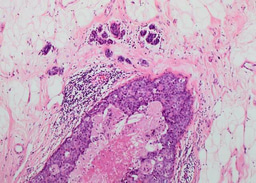

Professor John Sloane